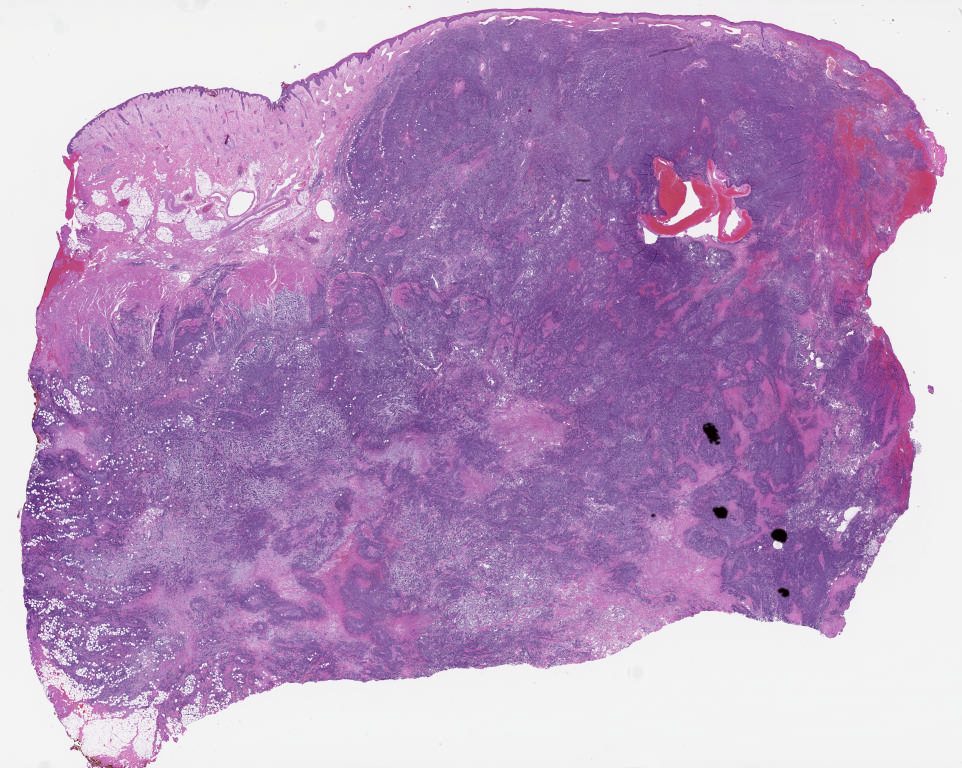

Case01.svs

69720

x

43834

@

20X